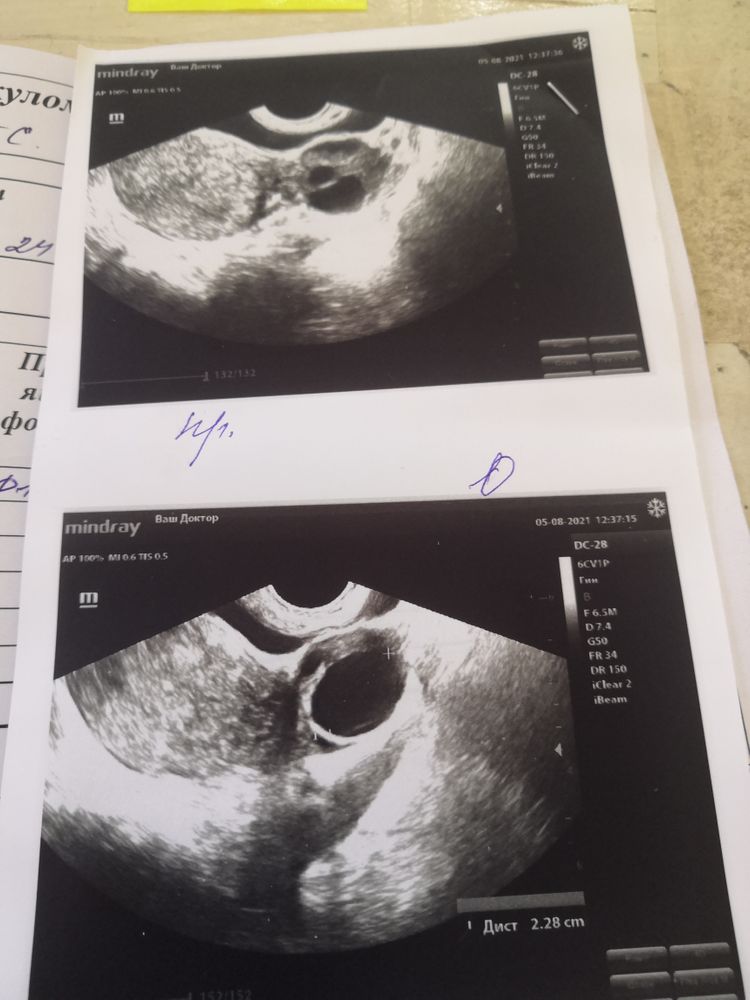

Сегодня 11 дц. Сильно болел левый яичника на 7 дц. Побежала сегодня на фолликулометрия. Думала скажут овуляцию уже прошла. А мне сказали что очень маленькая эндометрия 5.5ММ и надеяться не на что. Как помочь наростить эндометрия? Повторно на узи пойду ещё в понедельник.

05.08.2021